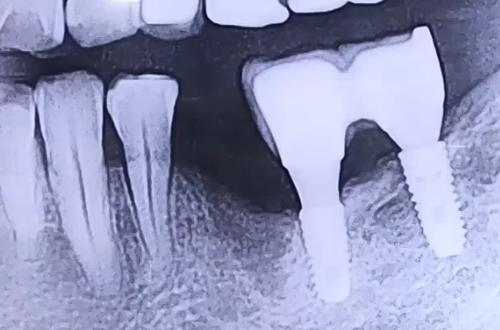

약해진 잇몸뼈에 식립한 작은 어금니 임플란트 사례

BEFORE

왼쪽 작은 어금니 발치 후 시간이 오래 지났고, 이전에 다른 치과에서 윗니, 앞니, 왼쪽 위아래 어금니 임플란트를 한 상태로 빈 어금니 부분에 추가 임플란트 치료를 받길 원하셔서 내원해 주신 환자분이십니다.

이를 빼고 오랜 시간이 지났기 때문에 그 자리의 잇몸이 약해져 있었고, 이전 치료 받은 아래 어금니 임플란트도 낮아진 잇몸을 보강하지 않은 듯 보였는데요.

약한 잇몸뼈에 맞춰 그대로 얇은 임플란트를 사용하면 어금니의 기능을 제대로 수행하기 어려우므로 뼈이식으로 잇몸의 폭과 높이를 충분히 회복시킨 뒤 튼튼한 임플란트를 식립해 치료해 드렸습니다.